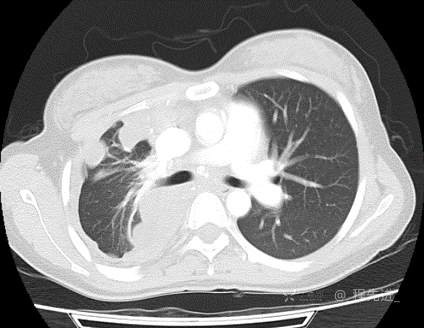

患者性别:女

患者年龄:26岁

简要病史:反复胸闷、气喘、咳嗽半年